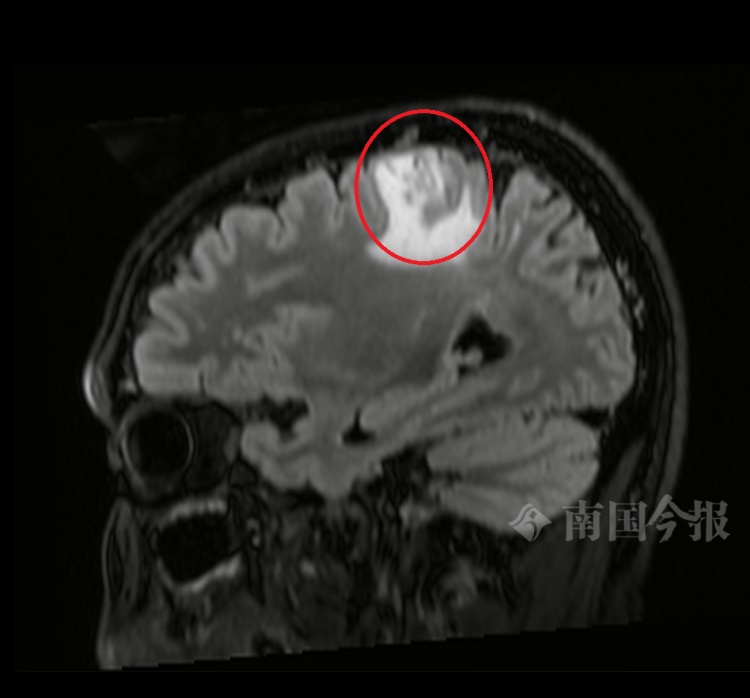

图为患者颅内占位性病变。

前往当地医院检查后,医生发现李先生的颅内存在占位性病变,考虑为食源性感染导致的颅内寄生虫病,需要进行手术治疗。该病变区域位于中央前回,属于肢体运动功能区,手术风险颇高。为了得到更优质的医疗救治,李先生前往广西脑科医院就诊。

经与患者沟通,广西脑科医院医疗团队决定迎难而上。术前,医疗团队通过高场强磁共振(MRI)对虫体进行精确定位。手术过程中,医生在毫厘之间精准操作,成功将寄生虫及其周围的病变组织一并清除,最大限度地保护了患者的正常脑组织。